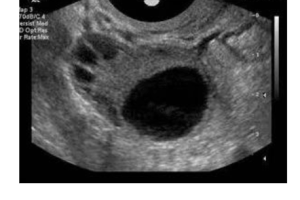

卵泡监测有什么用 卵泡监测是针对女性不孕的一种检查方法,能够通过卵泡检查发现女性不孕的病因,在试管婴儿手术中,卵泡监测技术也被普遍运用,期作用如下: 1、根据卵泡监测报告分析女性是卵泡发育问题还是排卵障碍问题; 2、试管婴儿中卵泡监测的用处主要是为了观察卵泡发育情况,以确定是否促排成功,制定取卵时间…

二维彩超

二维彩超多少钱做一次 单次二维彩超费用并不高,大概是在100元左右,不同地区、医院之间可能存在差异,建议以实际数据为准。虽然从单次缴费来看,二维检查并不贵,但孕期又何止是做一次这项检查,如果将这些检查次数累加在一起,那么不得有个一千好几。 一般来说,三甲以上的医院在二维彩超收费上面算比较便宜的,所以…